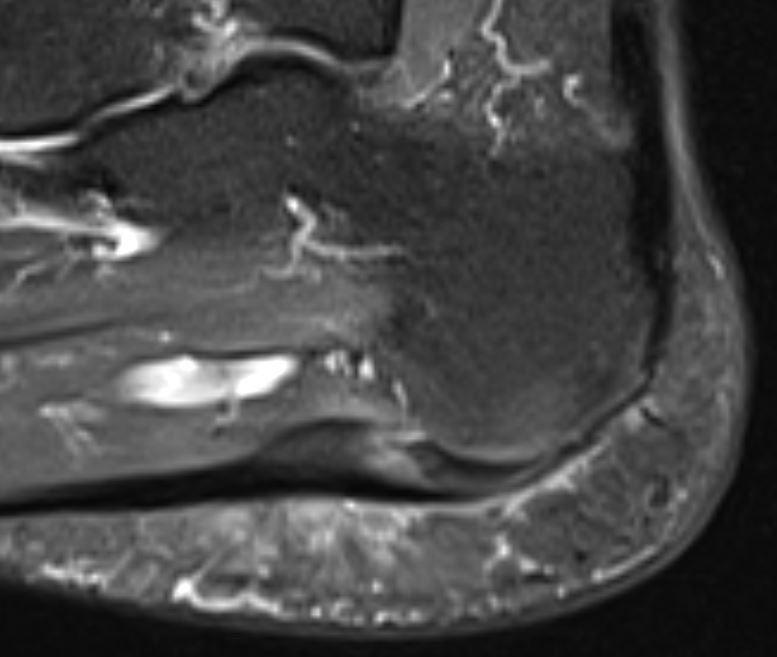

Home Schwerpunkte Krankheitsbilder Plantarfasziitis und Fersensporn – Schmerzen unter der Ferse loswerden! Plantarfasziitis im MRT sagital PD Fersensporn entzündet

Plantarfasziitis im MRT sagital PD Fersensporn entzündet